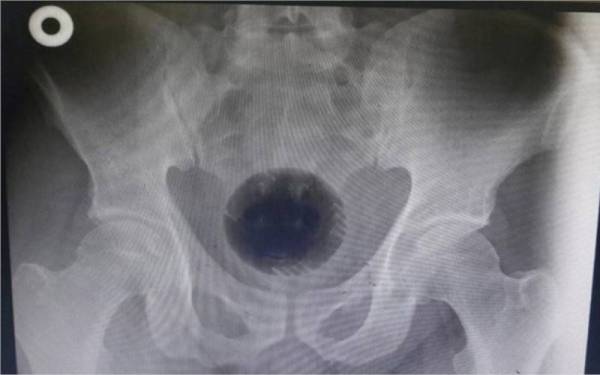

Sebelum pembedahan itu, lelaki berusia 51 tahun dikejarkan ke hospital selepas sebiji bola bersaiz 8 sentimeter (cm) tersekat dalam duburnya.

Kemudian doktor yang menjalankan inar X-ray dan imbasan CT untuk mengesan bola tersebut dan bergegas menggunakan kaedah lapartomi atau pembedahan untuk menolaknya keluar, menemui kegagalan.